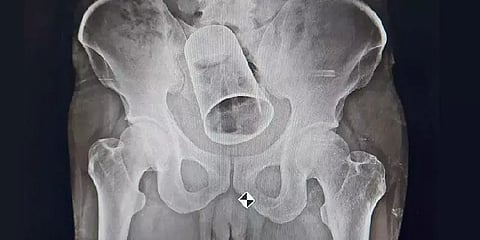

இதற்கிடையே ராவுத்தின் வயிறு வீங்கி, கடுமையான வலியை அனுபவித்துள்ளார். அவரின் நிலையை கண்ட குடும்பத்தார் கஞ்சம் மாவட்டத்திலுள்ள பெர்ஹம்புர் MKCG மருத்துவ கல்லூரி மருத்துவமனையில் சிகிச்சைக்காக கடந்த வெள்ளிக்கிழமை சேர்த்துள்ளனர். அதற்குள் தம்ளர் மலக்குடல் வரை சென்றுவிட்டது. மருத்துவர்கள் அவரை பரிசோதித்தபோதும் ராவுத் தனது மலக்குடலில் தம்ளர் இருப்பதை அவர் சொல்லவில்லை. எக்ஸ்-ரே எடுத்து பார்த்தபோதுதான் வயிற்றுக்குள் தம்ளர் இருந்ததை மருத்துவர்கள் கண்டு அதிர்ச்சியடைந்ததாக கூறுகிறார் அறுவை சிகிச்சை துறை உதவிப் பேராசிரியர் சஞ்சித் நாயக்.

தம்ளரை எப்படி அகற்றினார்கள் என்பதை விளக்கியுள்ளார் அறுவைசிகிச்சை பிரிவு பேராசிரியர் சரண் பாண்டா. ’’எக்ஸ்ரே எடுத்து பார்த்த உடனே வயிற்றுக்குள் இருந்த தம்ளரை அறுவைசிகிச்சை மூலம் எடுக்க நாங்கள் மருத்துவர் குழுவை தயார் செய்தோம். ஏனென்றால் அவருடைய நிலைமை மோசமாக இருந்தது. முதலில் தம்ளரை ஆசன வாய் வழியாக வெளியே எடுக்க முயற்சி செய்தோம். ஆனால் நோய்த்தொற்று ஏற்படுவதற்கான வாய்ப்புகள் அதிகம் இருந்ததால், கொலோஸ்டமி மூலம் வயிற்றை கிழித்தே அறுவைசிகிச்சை செய்ய முடிவெடுத்தோம். மலக்குடல் பகுதியில் சிக்கியிருந்த தம்ளரை வெளியே எடுக்க கிட்டத்தட்ட 2.5 மணிநேரம் ஆனது.